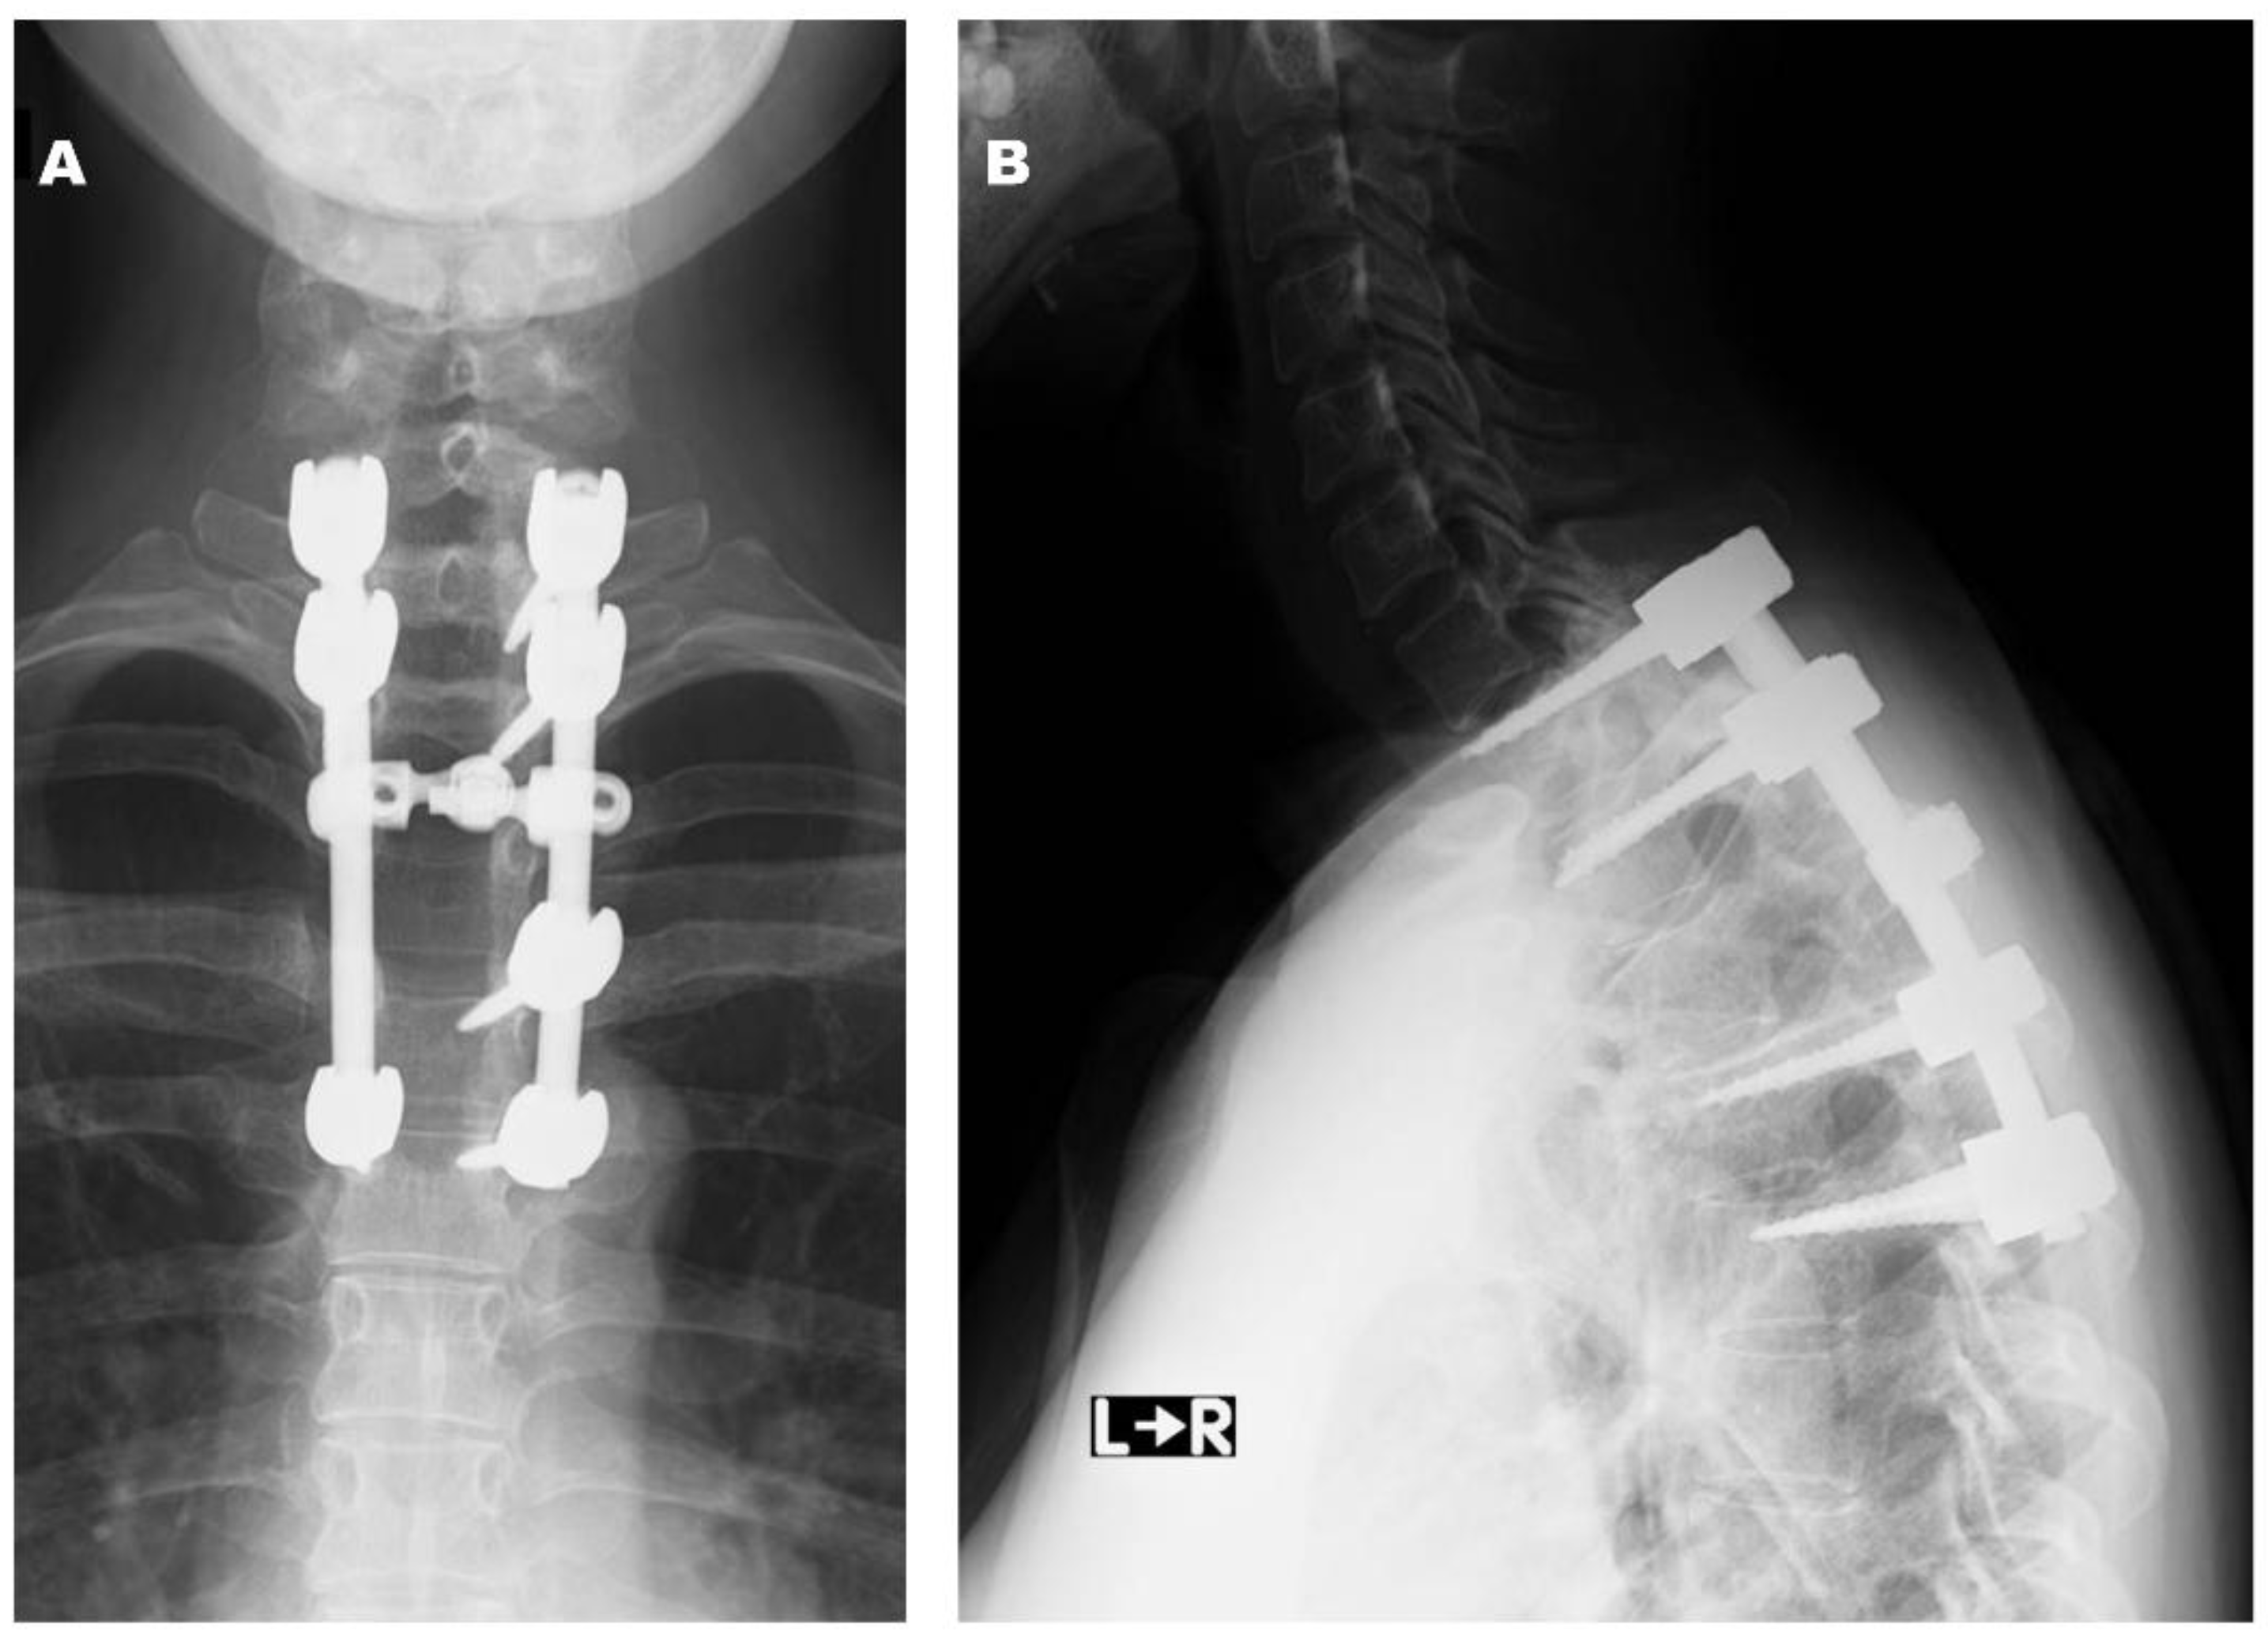

2.2. Case 2